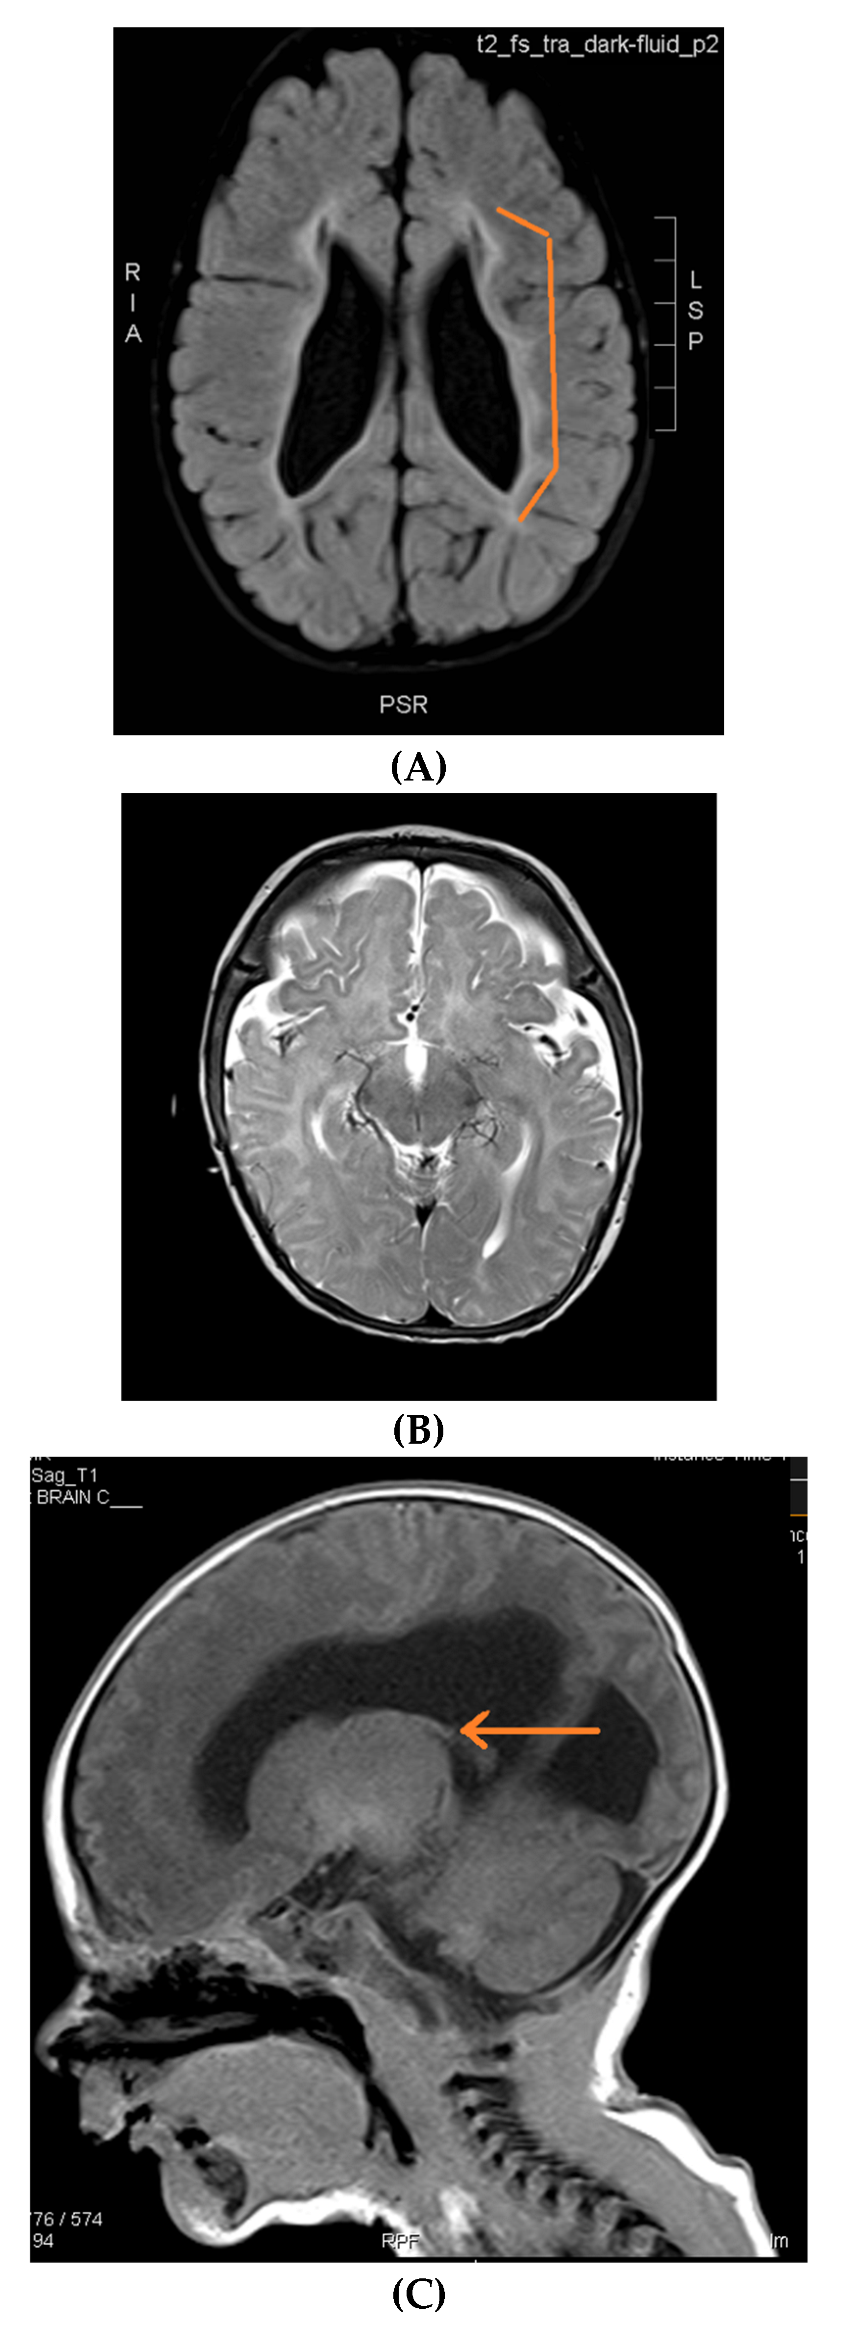

Brain MRIs showing the following (A): signs of hypoxia (T2 axial) with diffuse periventricular leukomalacia, enlarged ventricles and global atrophy (arrows); (B): delayed myelination in a 2-year-old child with diffuse hyperintense white matter compared to gray matter and brainstem (T2 axial); (C): dysgenesis of corpus callosum affecting its rostrum, genu, trunk and splenium (T1 sagittal) (arrows); (D): diffuse brain atrophy with enlarged ventricles (T1 axial); (E): severe ventricular dilatation (T2 axial) in a child with congenital muscular dystrophy; (F): intraventricular hemorrhage III (arrows) and hydrocephalus (T1 axial); (G): periventricular leukomalacia (T2 axial) (arrows); (H): non-specific white matter changes right precentral (T2 coronal) (arrows); (I): right frontal cortical tuber in a child diagnosed with tuberous sclerosis (T2 axial) (arrows); (J): PVL and frontal pachygyria (T2 axial) (arrows).